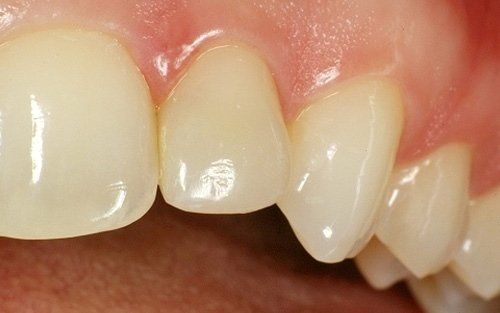

Il laterale di sinistra dopo la rimozione del vecchio restauro. Anche in questo caso tutto il tessuto sano della paziente è stato mantenuto.

Il laterale di sinistra ultimato.